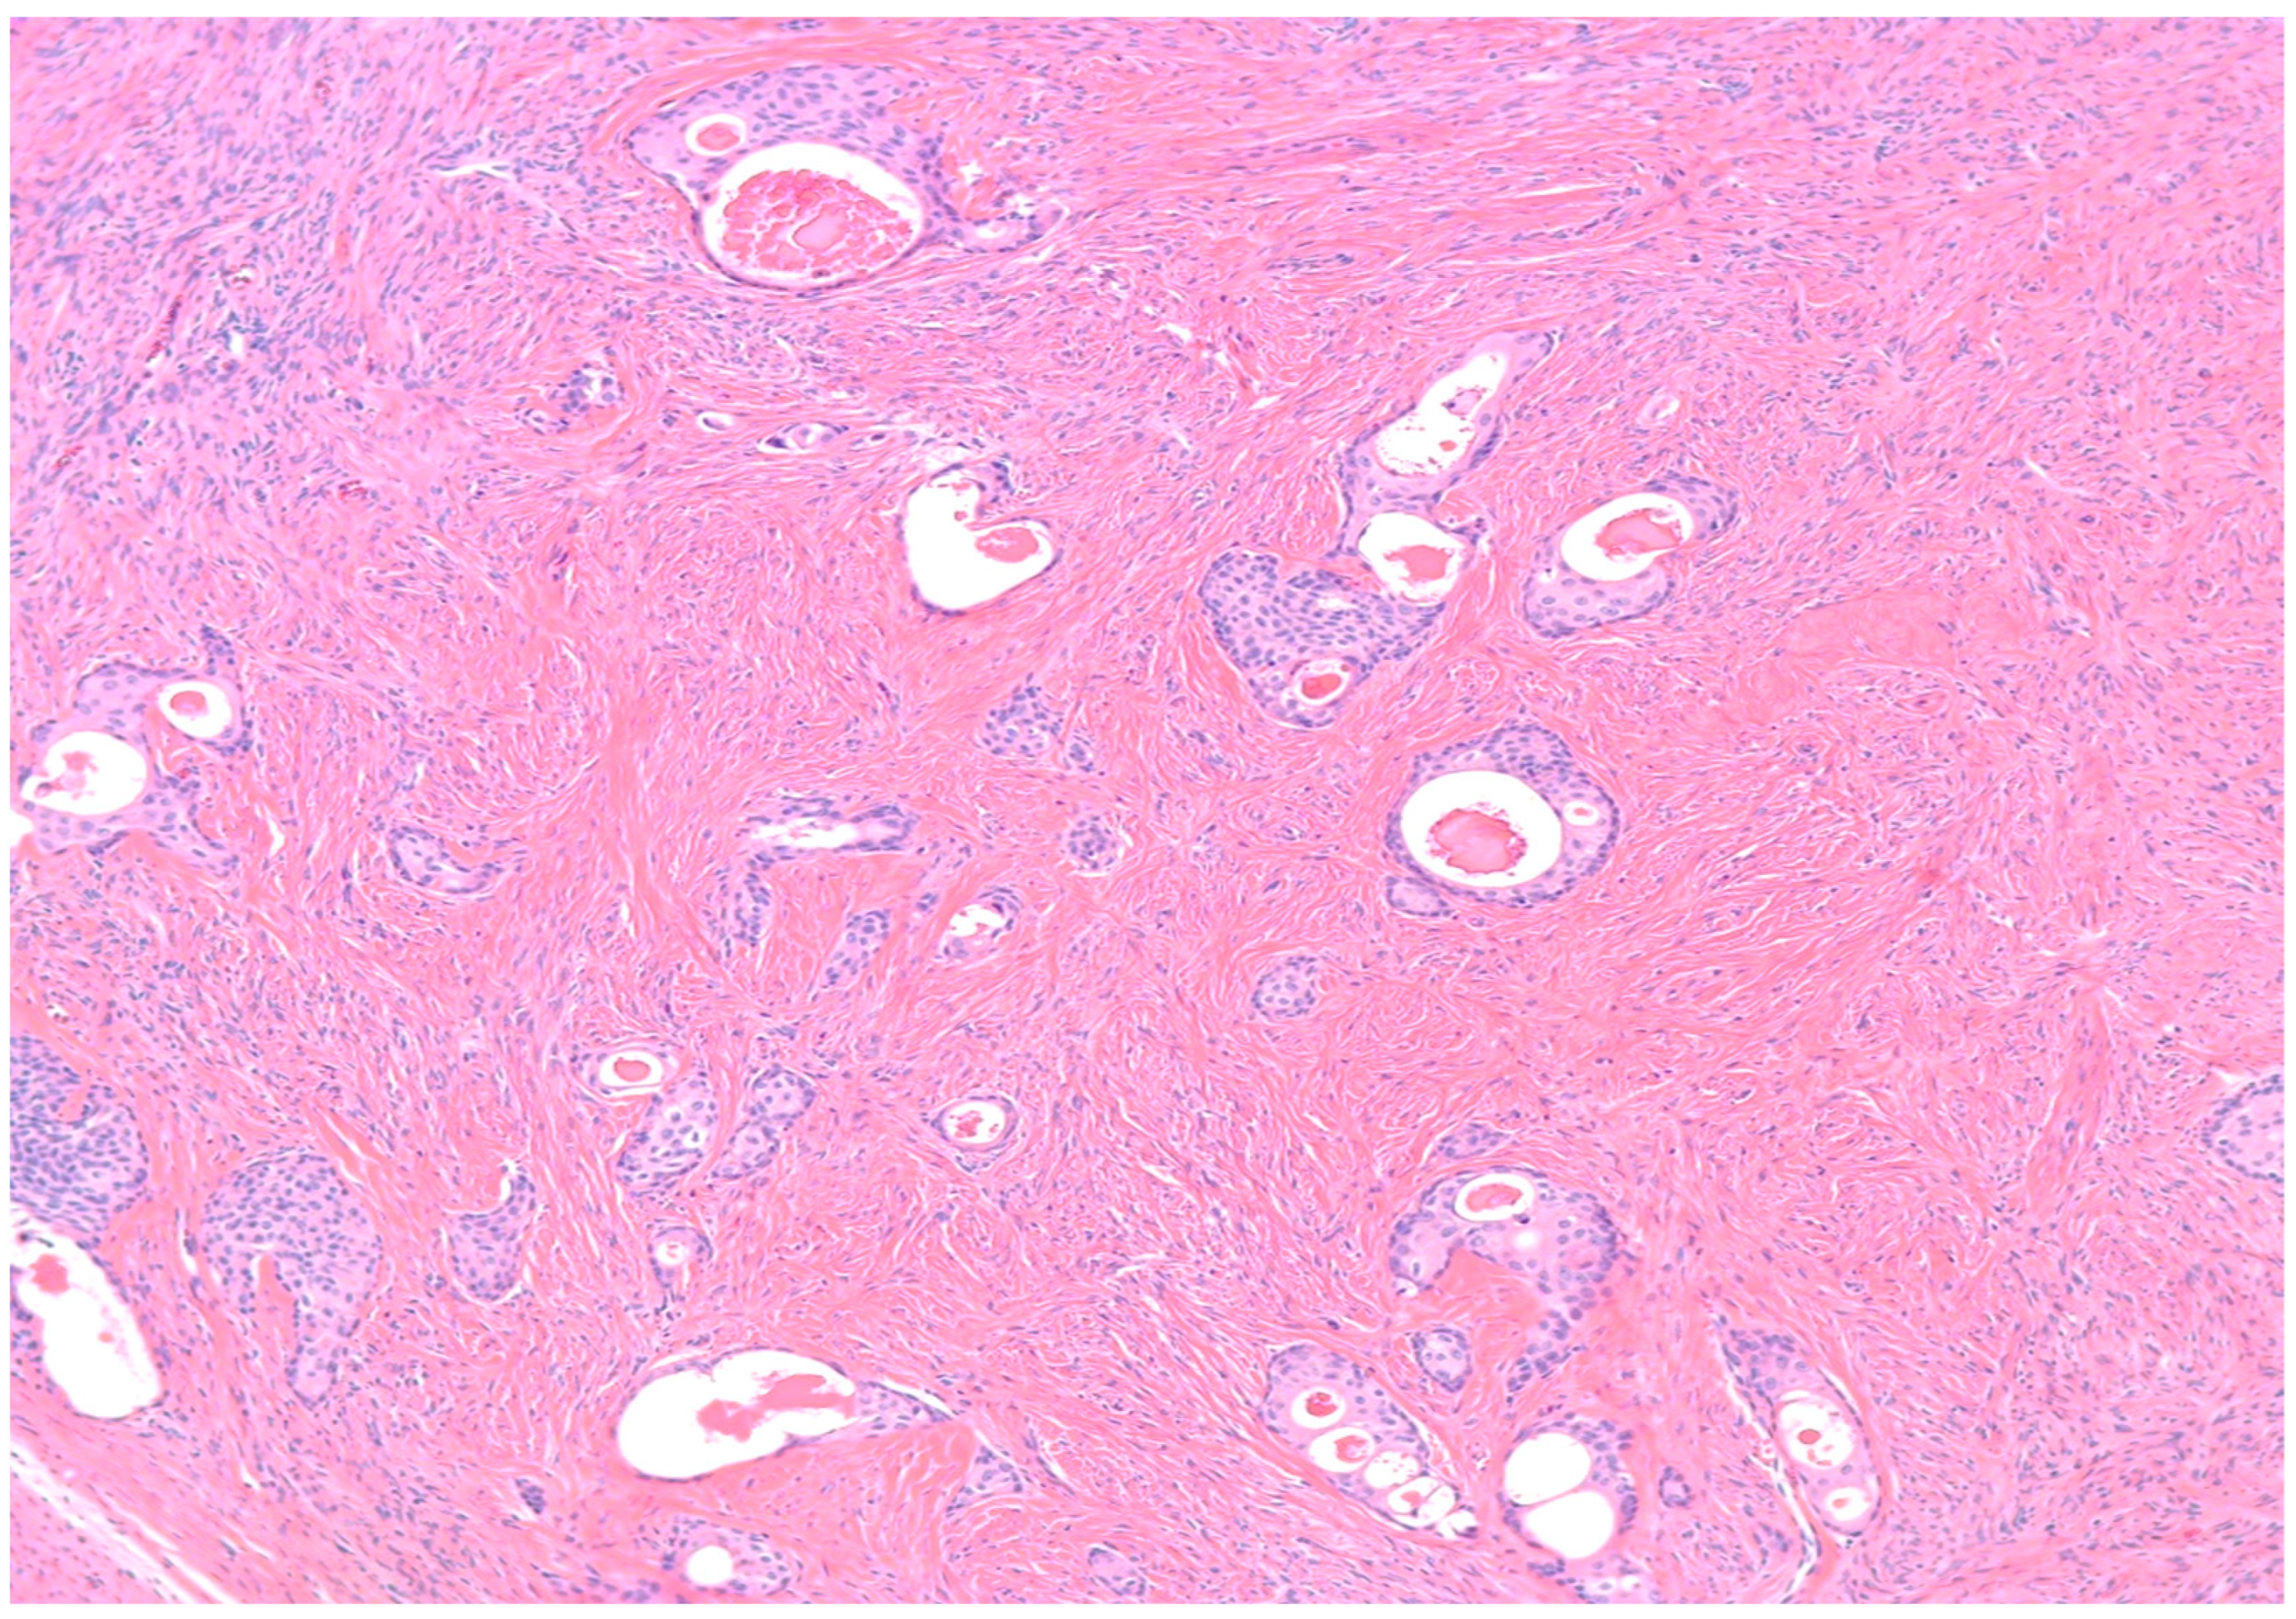

- Walthard cell rests: The differential diagnosis of benign BTs includes Walthard cell rests. Benign BTs contain a fibromatous background which is absent in Walthard cell rests.